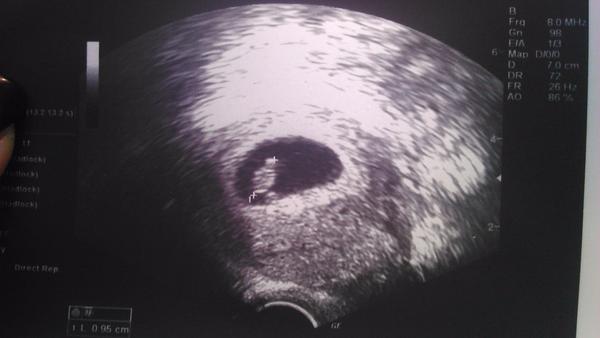

@kirip ahoj áno už som bola včera videli sme malú fazuľku 🙂 ešte však nebolo vidieť reakcie srdca, takže mám prísť budúcu stredu a potom urobí aj odbery. Tak dúfam, že bude všetko v poriadku ☹ to aj mne bude detí ľúto ešte v júni spolu ideme do SVP tak si ju poriadne užijeme. 🙂

@kirip tak prehliadka za nami 🙂 ôsmy týždeň fazuľka už má 1cm za posledných 10 dní narástla o 7mm 🙂 srdiecko nám bije o sto šesť 🙂 vy ako pokračujete? 🙂

Ahoj myska, teda je to tam🙂)))))))))))) tesim sa s tebou a dufam ze bude vs. v poriadku🙂 teda cca 10. teho na kontrolu...OK🙂 to by si uz mala nieco vidiet, ale keby si vydrzala do 8tyzdna...budes vidiet aj srdiecko..a pocut🙂 Tak co? pockas? Inak nastupuje ti kludovy rezim🙂 detom volno, ty pohoda, nohy na katedru🙂)))))))))